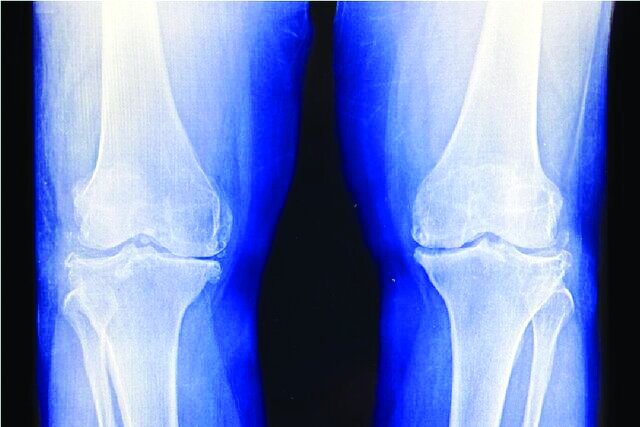

دانشمندان می‌گویند پرتودرمانی با دوز پایین، درد آرتروز زانو را تسکین می‌دهد و عملکرد زانو را بهبود می‌بخشد و می‌تواند جراحی تعویض مفصل زانو را در افراد مبتلا به آرتروز شدید به تأخیر بیندازد.

آگاه: در یک کارآزمایی بالینی، ۶جلسه پرتودرمانی با دوز پایین به طور قابل توجهی درد آرتروز زانو را کاهش داد و عملکرد زانو را برای ماه‌ها پس از آن بهبود بخشید که به جایگزینی ایمن و بدون دارو برای میلیون‌ها نفر مبتلا به تخریب مفصل اشاره دارد.

برای افرادی که مبتلا به آرتروز پیشرفته(OA)  زانو و درد شدید، تورم و کاهش شدید عملکرد همراه با آن هستند، نقطه پایانی، اغلب جراحی تعویض مفصل زانو است. بنابراین رویکردهای جایگزینی که درد را کاهش دهند و در عین حال عملکرد را بهبود بخشند و جراحی را به تأخیر بیندازند، مورد استقبال قرار می‌گیرند.

به نقل از نیو اطلس، نتایج یک کارآزمایی بالینی جدید به رهبری کالج پزشکی دانشگاه ملی سئول که در نشست سالانه انجمن آمریکایی انکولوژی پرتودرمانی(ASTRO)  ارائه شد، نشان داده است که چگونه یک دوره پرتودرمانی با دوز پایین می‌تواند درد را تسکین داده و عملکرد را در افراد مبتلا به آرتروز خفیف تا متوسط ​​زانو بهبود بخشد.

دکتر بیونگ هیوک کیم(Byoung Hyuck Kim)، محقق اصلی این آزمایش و استادیار انکولوژی پرتودرمانی در مرکز پزشکی بورامائه(Boramae)  دانشگاه ملی سئول گفت: افراد مبتلا به آرتروز دردناک زانو اغلب با انتخاب دشواری بین خطرات عوارض جانبی داروهای مسکن و خطرات جراحی تعویض مفصل مواجه هستند. بنابراین نیاز بالینی به مداخلات متوسط ​​بین داروهای مسکن ضعیف و جراحی تهاجمی وجود دارد و ما فکر می‌کنیم پرتودرمانی ممکن است گزینه مناسبی برای این بیماران باشد، به خصوص زمانی که داروها و تزریقات به خوبی تحمل نمی‌شوند. چکیده این مطالعه در وب‌سایت نشست سالانه ASTRO ۲۰۲۵ موجود است.